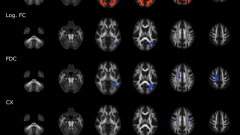

We identified a decrease of intracellular volume fraction (ICVF), decrease of isotropic volume fraction (ISO) and decrease of orientation dispersion index (ODI) in multiple inferior frontal regions of interest in COVID-19 patients; this longitudinal change was significantly different from the control group which demonstrated increases in equivalent measures. This pattern suggests injury with neuronal loss and/or inflammation as underlying mechanisms. Neurocognitive studies identified a pattern of cognitive decline (processing speed, executive function, verbal learning, working memory) in patients, that did not reach significance.